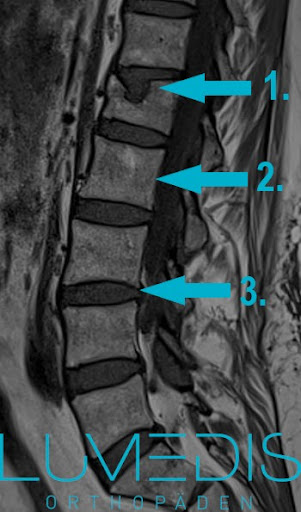

Dauer Eines Wirbelbruch Lumedis Wirbelsaulenspezialisten